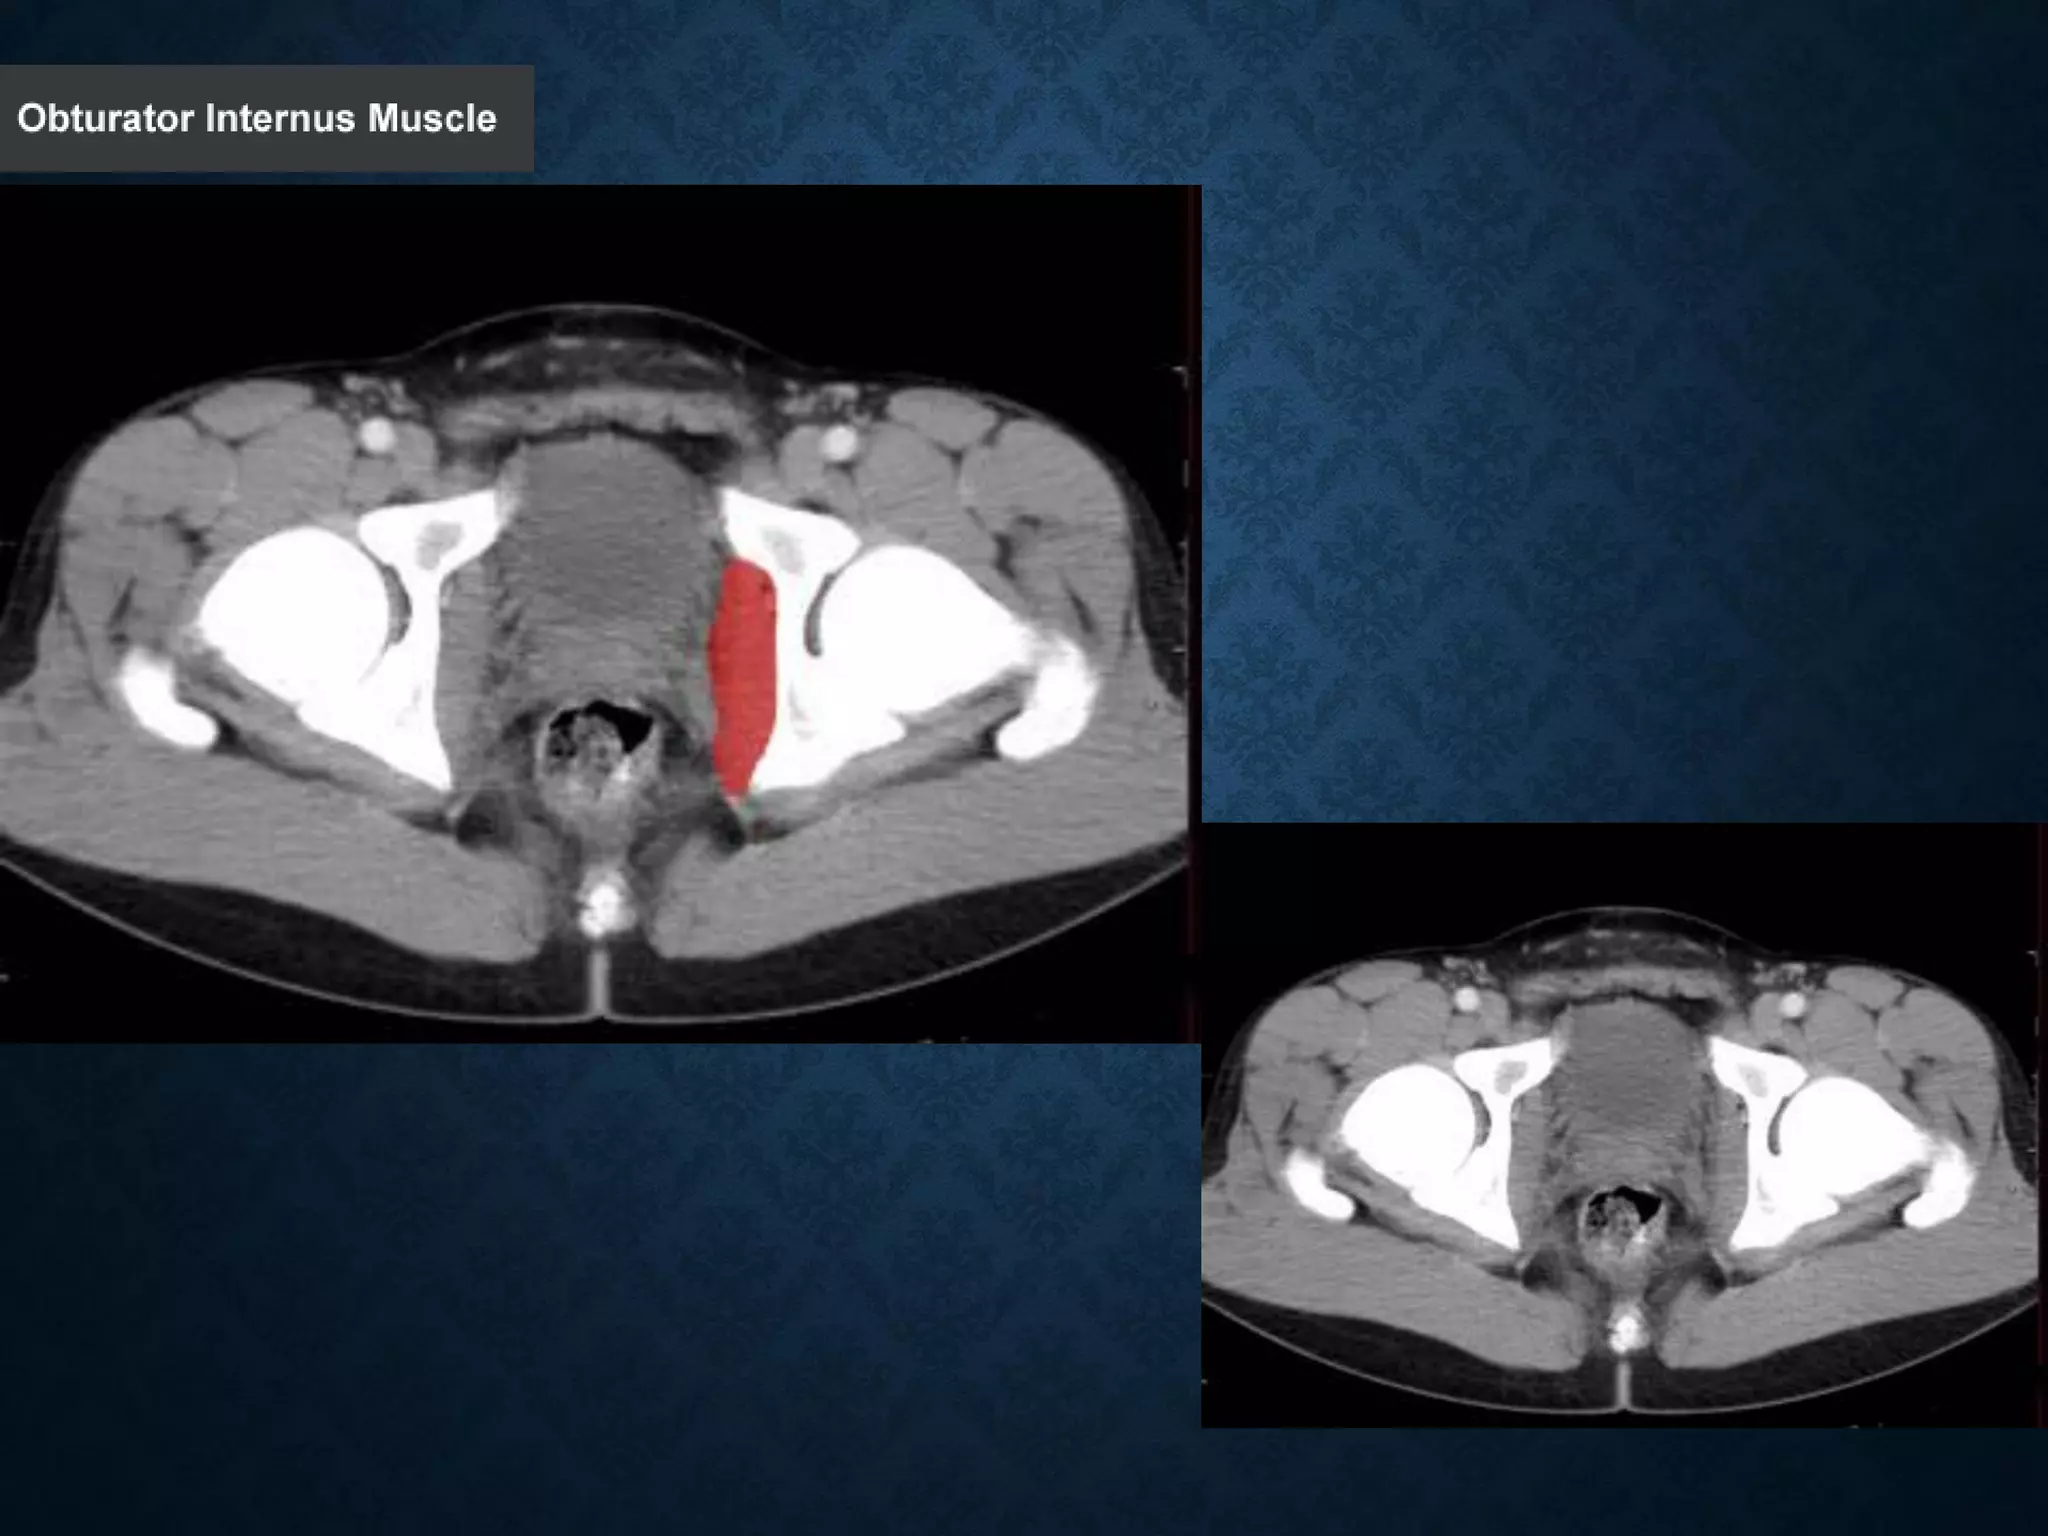

Identify the following structures in the body CT to the right. To view the location of the structure in the image click on

the label at the left and the structure will be indicated in the image. Abdominal CT scans typically begin just above

the diaphragm, so the first slice you see is of the lower chest.

Identify the followingstructures in the body CT to the right. To view the location of the structure in the image click on the label at the left and the structure will be indicated in the image. Abdominal CT scans typically begin just above the diaphragm, so the first slice you see is of the lower chest.